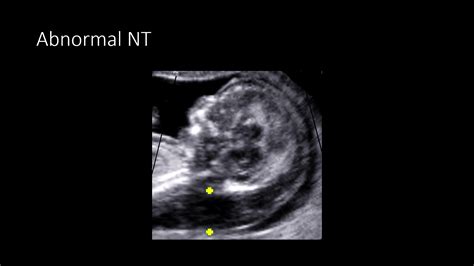

The nuchal translucency (NT) scan is a non-invasive prenatal screening test performed between 11 and 14 weeks of pregnancy. The term "nuchal" refers to the back of the neck, and "translucency" refers to the fluid-filled space located there. During this scan, a sonographer uses ultrasound technology to measure the thickness of the fluid collection at the back of the fetus's neck.

The scan is typically performed through an abdominal ultrasound. In some cases, if the baby’s position makes it difficult to get a clear view, a transvaginal ultrasound may be used. The sonographer will carefully maneuver the transducer to obtain a clear side-profile image of the fetus, known as the mid-sagittal plane. The measurement of the fluid space is extremely precise, often down to the millimeter.

When asking "what is NT screening," it is also necessary to understand what influences the interpretation of the results. The thickness of the fluid is not measured in isolation. A high measurement does not automatically mean there is a chromosomal abnormality; it simply indicates that further investigation is warranted. Other factors that influence the final risk assessment include: